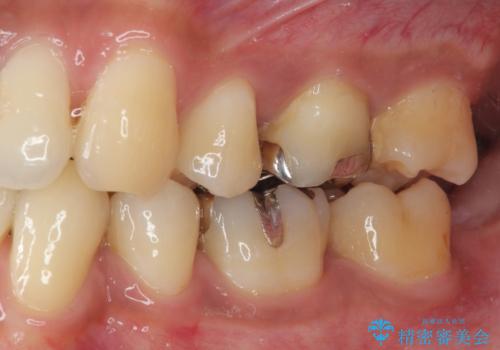

- 銀歯を外したいとのことで来院された患者様です。検査の結果、メタルインレーの範囲も大きいためオールセラミッククラウンにて補綴治療を行っていくことにしました。

拡大鏡視野下でメタルインレー、虫歯の除去を行いオールセラミッククラウンに適した形に整えました。

歯と歯茎の間に圧排糸と言われる糸を入れてシリコーン印象材にて型どりをしました。